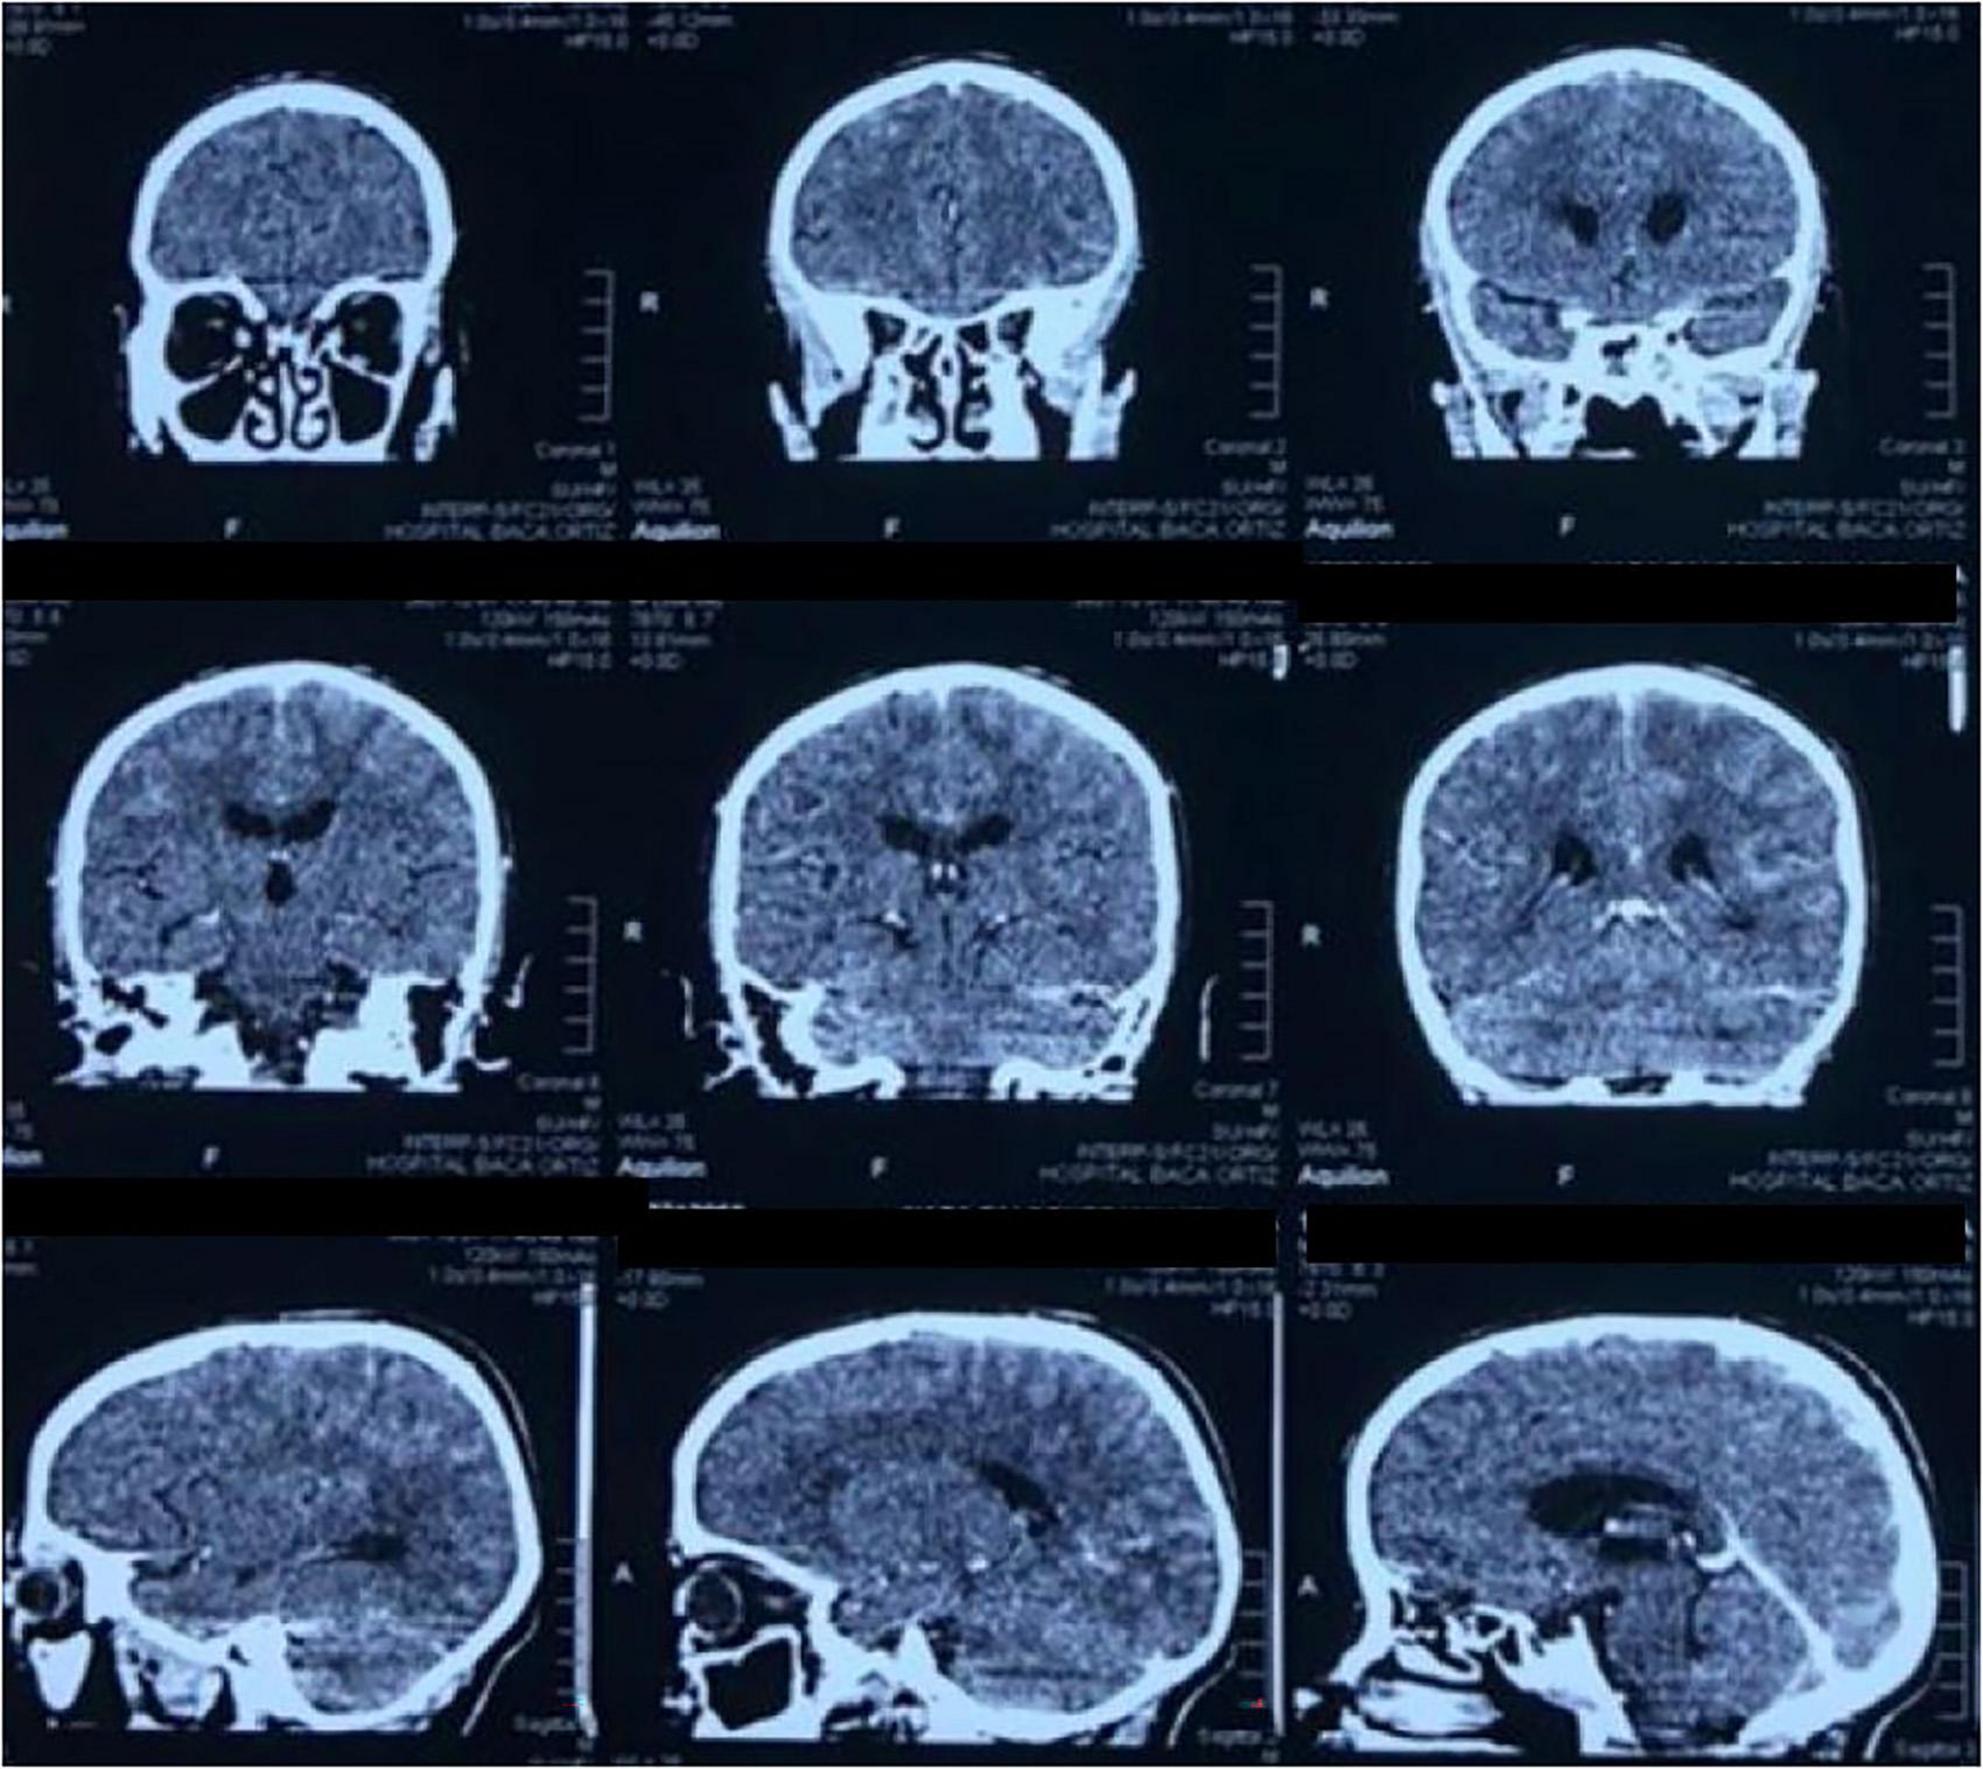

Neurological examination revealed nuchal rigidity and positive Kernig and Brudzinski signs. Laboratory tests showed an HIV viral load of 4,050 copies/mL and a CD4 count of 11 cells/mm3, consistent with WHO clinical stage IV AIDS. Cerebrospinal fluid (CSF) analysis revealed hypoglycorrhachia, positive India ink staining, and cultures positive for Cryptococcus neoformans in both CSF and blood. A FilmArray panel also confirmed the presence of Cryptococcus neoformans. A cranial computed tomography (CT) scan performed at admission showed no ventricular abnormalities or meningeal enhancement (Figure 1).

FIGURE 1

CT scan of the brain in coronal and sagittal planes shows a ventricular system with preserved morphology. No meningeal enhancement is observed.